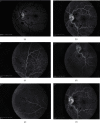

An unusual case of nitroglycerin-induced Paracentral Acute Middle Maculopathy (PAMM) is presented. A 50-year-old patient with sudden vision loss and scotoma was followed up with swept-source optical coherence tomography (SS-OCT), optical coherence tomography-angiography (OCT-A), and fluorescein angiography (FA). An anal fissure treated with glyceryl trinitrate (GTN) 0.2% ointment with headache and dizziness after application was reported. Fundoscopy OS revealed mild retinal venous dilatation and tortuosity with scattered blot hemorrhages and subtle, parafoveal, whitish lesions in the outer retina. SS-OCT revealed diffuse, hyperreflective lesions in the inner plexiform (IPL), inner nuclear (INL), and outer plexiform layers (OPL). OCT-A revealed focal dropout in the deep capillary plexus. FA showed masking due to blot hemorrhages and early punctuate leakage in the inner retina. This entity was identified as nitroglycerin-induced PAMM. Over the following 8 months, after discontinuation of the ointment application, the patient was symptom-free with stable visual acuity. OCT revealed INL/OPL thinning and confirmed complete lesion resolution. This first report of retinal vascular abnormalities due to nitrite ointment provides an insight into an unknown side effect of nitroglycerin ointment use. A dose-dependent correlation between GTN application and retinal vascular abnormalities remains to be confirmed.